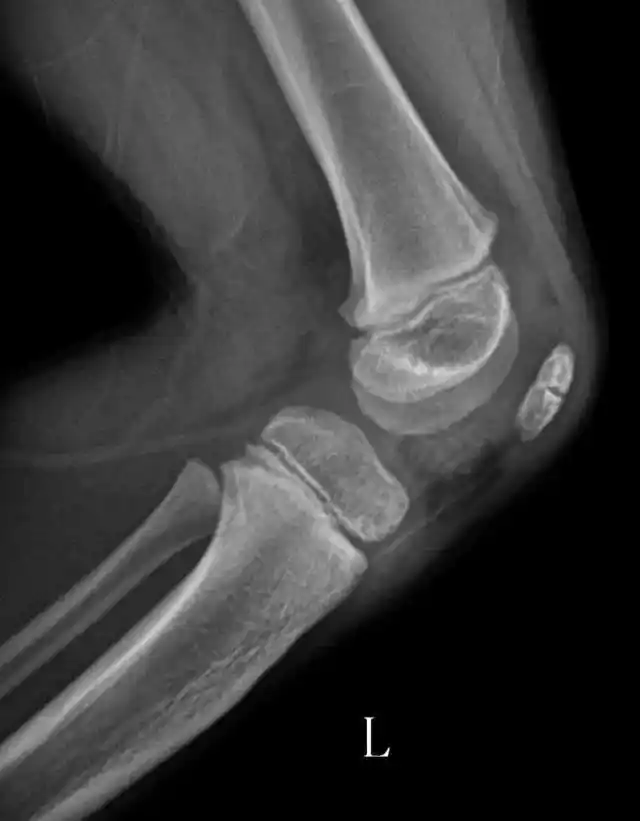

髌骨位置测量